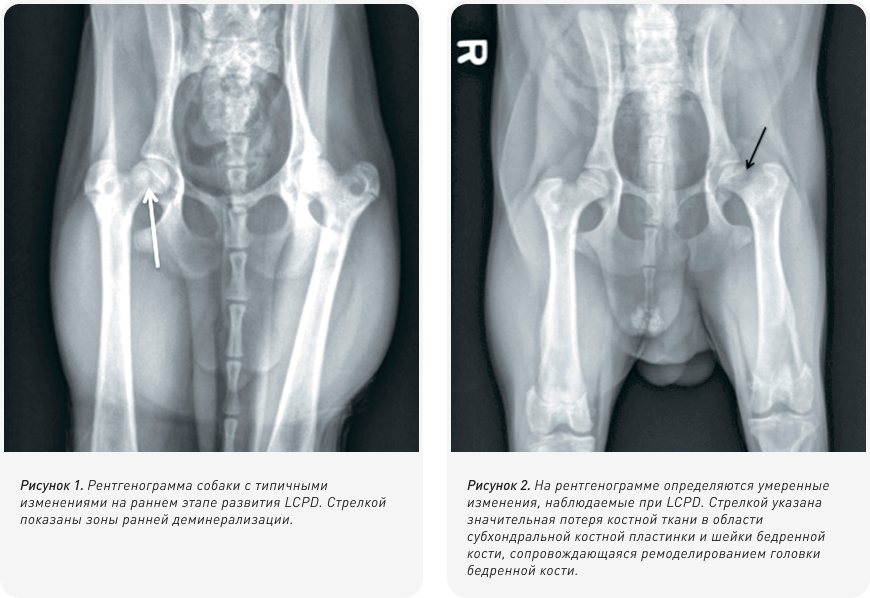

Хотя результаты клинического осмотра наряду с присутствием типичных симптомов позволяют с высокой степенью вероятности предположить LCPD, для подтверждения диагноза обычно также проводится рентгенография. На ранней стадии заболевания участки лизиса и деминерализации могут быть выявлены в субхондральной области головки и шейки бедренной кости (Рис. 1). По мере развития патологии может отчетливо проявляться коллапс головки и шейки бедренной кости (Рис. 2). На более поздних стадиях могут присутствовать признаки реминерализации и заживления костной ткани.

Могут наблюдаться изменения, связанные с развитием вторичного остеоартрита, включая формирование остеофитов (особенно по краю вертлужной впадины и на головке бедренной кости) и уплощение головки бедренной кости. Рентгенографические изменения, наблюдаемые по мере прогрессирования заболевания, были разбиты на категории по степени тяжести, как указано в Таблице 1.